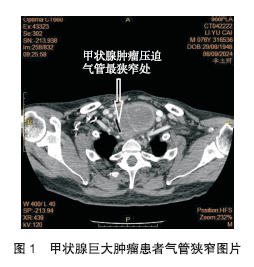

患者意识清晰,呼吸费力,可平卧但时间不超过2 h;颈部可闻及哨样呼吸音,气管偏右。颈部超声:左叶内可见大小4.8 cm×4.5 cm×7.0 cm 的不均质低回声团块,右叶内可见大小3.5 cm×2.4 cm、2.4 cm×1.8 cm 的不均质低回声团块,左叶上极靠近峡部还可见大小1.1 cm×1.0 cm的低回声团块,均形态规则,界限清晰。颈部CT 提示甲状腺左叶及峡部体积明显增大,似见两个类圆形囊性低密度影相融合,范围约为6.1 cm×5.0 cm×8.6 cm,气管受压向右侧移位,病灶与食管关系密切,分界不清,甲状腺右叶体积增大,约为3.1 cm×2.7 cm×5.6 cm,左侧颈总动脉及左侧锁骨下动脉受压移位。颈部软组织三维重建提示:甲状腺左叶见软组织团块,密度不均,大小为4.9 cm×5.1 cm×5.9 cm,向下延伸至胸廓入口,气管上段约T1-T2椎体水平局部受压狭窄,吸气相最狭窄处短径约0.26 cm,呼气相最狭窄处短径约0.38 cm,狭窄范围约为2.18 cm,狭窄处距气管隆突9.80 cm,狭窄处距声门约为7.40 cm(图1)。